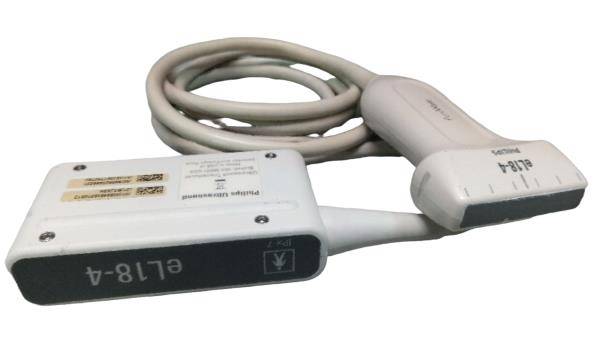

The Acuson Cypress Cardiac Vascular Ultrasound Machine is engineered for exceptional imaging and diagnostic accuracy. Its advanced technology allows for detailed visualization of cardiac and vascular structures, which is essential for healthcare providers. The inclusion of the 3V2c and 7L3 probes enhances its versatility, making it suitable for various clinical applications. As a result, this machine is a crucial tool in modern cardiology and vascular assessment.